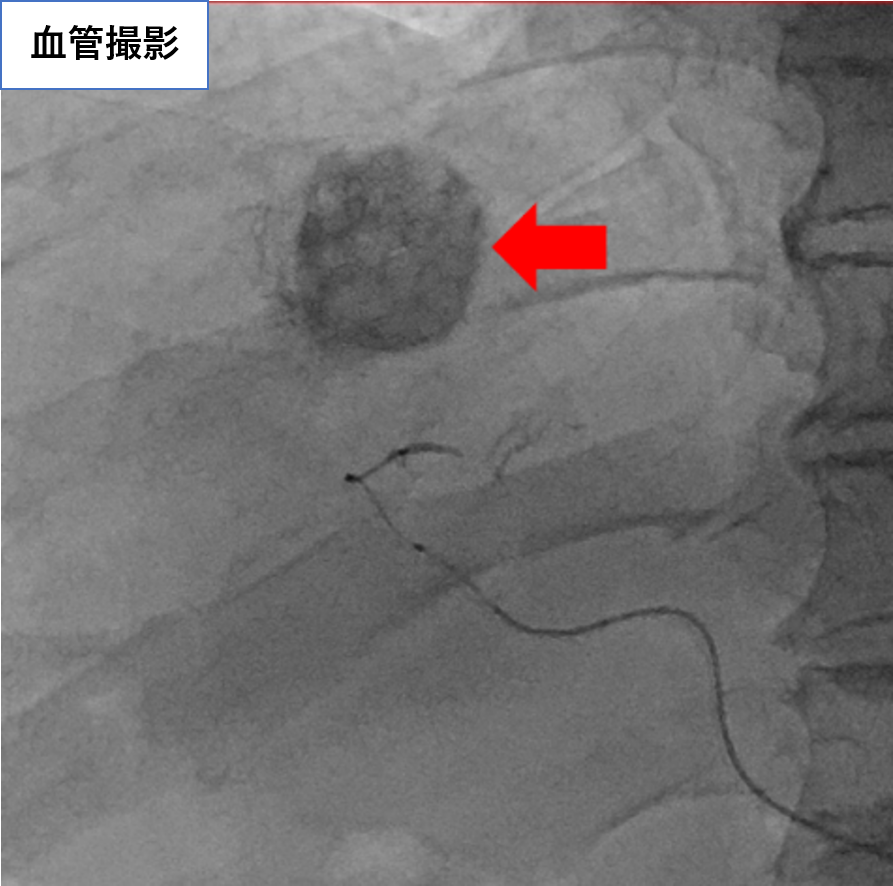

【治療例1:冠動脈科学塞栓術(TACE)】

カテーテルを用いて肝細胞がんに栄養を送る動脈を探し、がん細胞だけに抗がん剤を送り込みつつ、がんを栄養とする血管を詰める(塞栓)治療です。

治療前

治療後